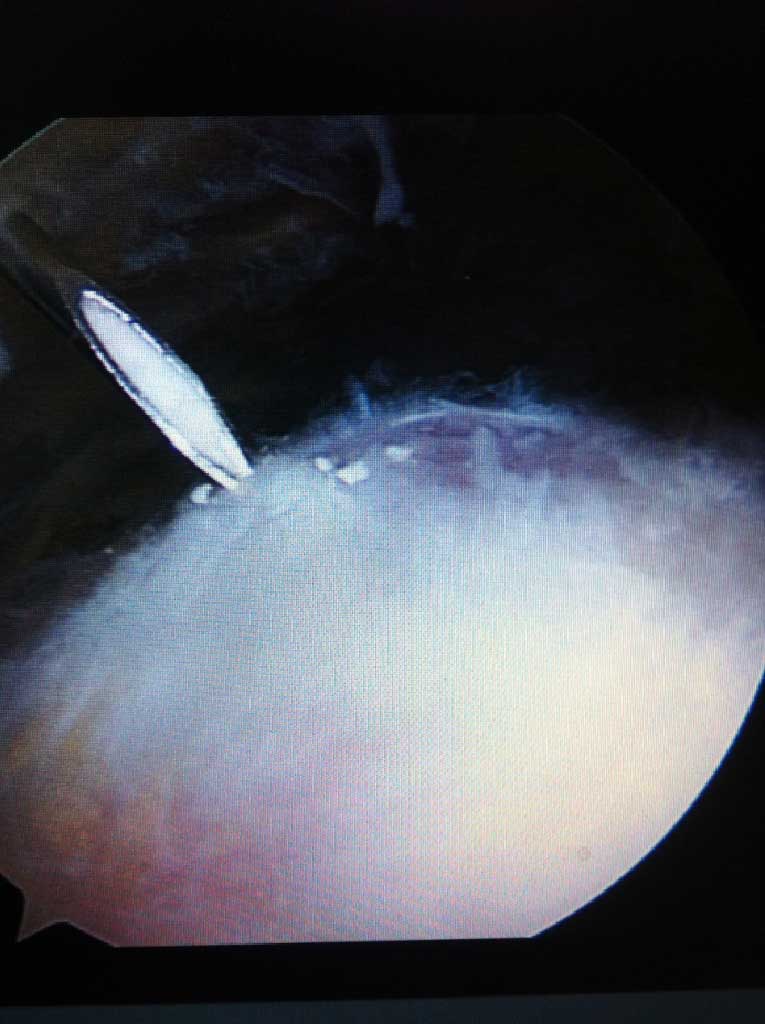

Die s.g. Tendinitis calcarea ("Kalkschulter") ist sehr häufige Ursache von akuten aber auch chronischen, manchmal ausgeprägten Schulterschmerzen.

Lässt sich die Schmerzsymptomatik durch konservative entzündungshämmende Therapie nicht lindern, so wird eine arthroskopische Kalkdepotausräumung empfohlen. Dabei, innerhalb 20-30 min wird das Kalkdepot aus der Schultersehne durch 3-5 kleinen Stichinzisionen entfernt und die Sehne anschliessend genäht. Die Nachbehandlung beträgt zirka 8-10 Wochen mit Krankengymnastik und ggf. anschließender Reha Maßnahme.